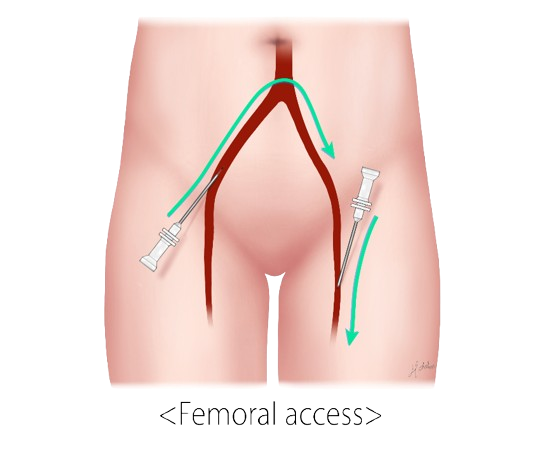

Genicular Artery Embolization (GAE) is a minimally invasive, image-guided procedure for treating chronic knee pain caused by osteoarthritis or related to chronic inflammation. It works by reducing blood flow to the inflamed areas of the knee, which can help relieve pain and improve mobility. Interventional radiologists will insert a small catheter (a thin hollow tube) into the artery of the patient’s upper thigh and, with the use of X-rays, guide the catheter to the arteries supplying the lining of the knee. Tiny particles are then injected through the catheter into these arteries, reducing the blood supply. This in turn reduces the inflammation associated with osteoarthritis, which alleviates the pain

- A small catheter is inserted into an artery (usually in the upper thigh)

- Using X-ray guidance, the catheter is advanced to the small arteries supplying the inflamed areas of the knee